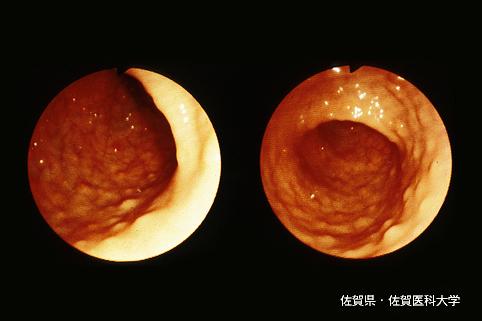

疾病(病理主体)的分类恶性淋巴系统・血液系统肿瘤/ATL (成人,ATL细胞白血病)

部位(按器官分)大肠/占据大肠的2个以上区域

检查方法内窥镜

肿瘤最大直径1~9

多发性肿瘤(同一器官)有(同时性)

多重性肿瘤(多个器官)有(同时性)